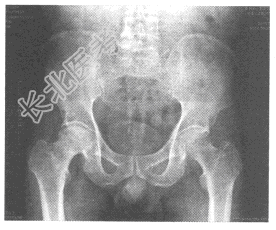

- 单项选择题男,49岁, 右髋部疼痛1年半,近1个月加重, 不发热,有饮酒史。根据骨盆平片, 最可能的诊断为

A、股骨头缺血坏死

B、髋关节结核

C、髋关节化脓性炎症

D、退行性骨关节病

E、强直性脊椎炎髋关节改变